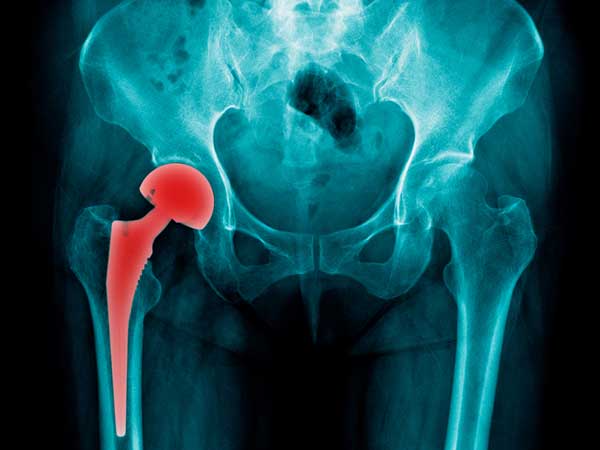

The Metal-on-Metal Hip Implants Scandal

If you suffer from hip problems, the results can be catastrophic, leading to debilitating pain that can rob you of your quality of life. Hundreds of thousands of people have turned to metal-on-metal hip implants in an effort to find relief. Unfortunately, many of these implants have reportedly caused severe complications, often necessitating the need for painful and expensive revision surgeries.

The problem of hip implant complications was so bad that officials with the U.S. Food and Drug Administration held a two-day meeting in 2012 to discuss the issue. According to an article that appeared on the Medical News Today (MNT) website, as many as 500,000 people could face risks due to defective implants. Several companies manufactured the implants in question, including Johnson & Johnson, Zimmer Holdings and others.

MNT reported that studies showed not only that people were falling ill due to metallosis, a condition in which pieces of metal enter the bloodstream and cause poisoning, but that the failure rate of certain implants was a lot higher than manufacturers let on.